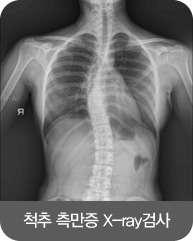

척추측만증은 여러가지 원인에 의하여 일자로 되어야 할 척추가 C자형 또는 S자형으로 휘어진 경우를 말합니다.

진단은 서있는 자세에서 양쪽 어깨 높이가 다르거나 등 뒤에서 환자를 봤을때 견갑골이 튀어 나오거나 척추가 휘어진 소견이 보이는 경우일 때 진단하며 정확한 진단을 위해서는 전신X-ray(엑스레이) 검사가 중요하며 검사를 통해 측만증의 부위, 정도 등을 진단하게 됩니다.

※ 자가진단법 : 환자를 똑바로 서게 한 뒤에 등을 몸 앞 쪽으로 90도 정도 숙이게 하고 뒤쪽에서 등의 높이가 대칭을 이루지 않고 한쪽이 더 높게 나타나면 진단할 수 있습니다.